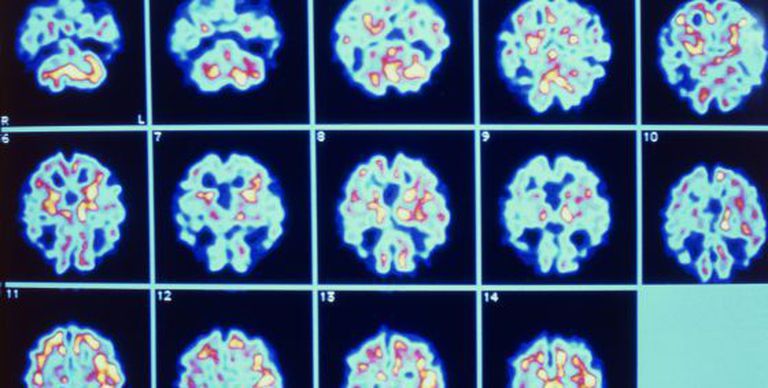

Essa enfermidade neurodegenerativa se desencadeia pela morte neuronal vinculada à presença de duas estruturas aberrantes no cérebro: a proliferação das chamadas placas senis (depósitos do peptídeo beta-amiloide) e a formação dos emaranhados neurofibrilares (um conglomerado de pequenas fibras de proteína).

O estudo descreve o PLD3 como uma peça-chave nessa complexa enfermidade a respeito da qual, exceto pelos exames da sua vinculação genética, não existe um consenso científico sobre os mecanismos biológicos que a desencadeiam. Os pesquisadores observaram em cultivos que altos níveis de expressão do gene e da presença da proteína estavam relacionados aos baixos níveis de beta-amiloide, enquanto que, no caso contrário, aumentavam os níveis do peptídeo, cuja acumulação em placas é um dos traços da doença. Esse mesmo fenômeno foi observado em amostras do tecido cerebral obtido de pessoas afetadas, em comparação a pessoas sem o Alzheimer.